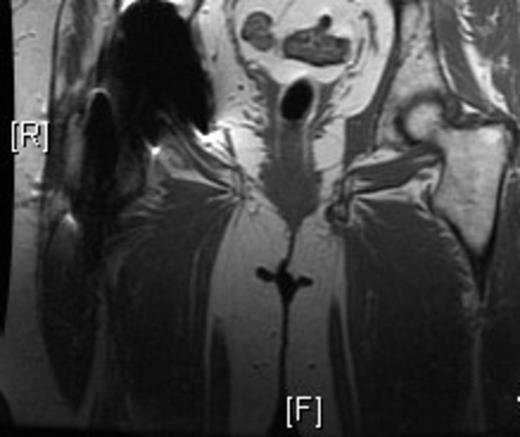

Representative images, including: a plain radiograph (Figure 1), 3D reconstructed computed tomography (Figue 2) and T1 coronal magnetic resonance imaging (Figure 3) indicated a bony excrescence from the inferior aspect of the left ischium measuring 1.7 x 1.1 cm. MR without gadolinium did not show any surrounding inflammatory changes. No aggressive features were seen on the studies. Review of a previous CT scan from 2 years prior to the most recent study, demonstrated a stable lesion.

The above studies were suggestive of a pelvic digit. The patient’s chief complaint was painful intercourse and she elected to proceed with a resection. A pelvic digit was further confirmed after resection (Figure 4). Pathology found no evidence of malignancy and the patient was discharged without pain and able to ambulate without support of a walker. The removed pelvic digit had two bony segments that formed a pseudoarticulartion or joint, visible in images A and B. Follow up via a telephone communication indicated that her dyspareunia had resolved.